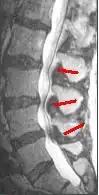

CT scan of spinal stenosis and thickened ligamentum flavum, causing neurogenic claudication